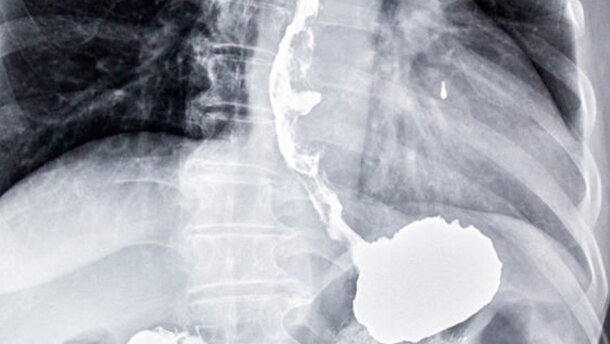

I medici effettuano la diagnosi di tali tumori tramite endoscopia. Tuttavia, la procedura è invasiva e costa al servizio sanitario nazionale circa 400–600 sterline (circa 560–850 euro) per ogni endoscopia. Solo al 2 per cento dei pazienti sottoposti a endoscopia è stato diagnosticato con cancro esofageo o gastrico. «Il cancro dello stomaco e dell’esofago sono in aumento con oltre 16.000 nuovi casi diagnosticati ogni anno ‒ dichiarato George Hanna, autore principale dello studio e Direttore delle NIHR-Diagnostic Evidence Cooperatives (Imperial College London) ‒. L'attuale metodo per la rilevazione di questi tumori è costoso, invasivo e la diagnosi viene di solito effettuata in una fase tardiva, quando spesso si è diffuso in altre parti del corpo. Questo rende la malattia più difficile da trattare e si traduce in scarsi tassi di sopravvivenza a lungo termine. Il nostro “breath test” potrebbe risolvere questi problemi, perché aiuta a fornire una diagnosi ai pazienti che manifestano primi sintomi non specifici, nonché riduce il numero di endoscopie invasive, che spesso portano a risultati negativi. La diagnosi in una fase iniziale potrebbe offrire ai pazienti più opzioni di trattamento e, infine, salvare più vite umane»

Per eseguire il test, i pazienti respirano in un dispositivo simile a un etilometro collegato ad un sacchetto. Il test cerca i composti chimici nel condensato del respiro specifici per ogni paziente con cancro esofageo o gastrico. I tumori producono un caratteristico odore di composti organici volatili (VOC), sostanze chimiche contenenti carbonio, che si trovano in tutti gli esseri viventi. Questo potrebbe aiutare i medici a rilevare i primi segnali della malattia.

I ricercatori sono stati capaci di identificare per la prima volta la quantità dei composti chimici VOCs emanati col respiro usando uno spettrometro di massa SIFT-MS (selected-ion flow-tube mass spectrometry), strumento analitico utilizzato per identificare le sostanze chimiche presenti in un campione. Questa tipo di tecnologia quantitativa ha identificato i VOCs, presenti in concentrazioni significativamente più alte nei pazienti con cancro esofageo o gastrico rispetto a quelli senza cancro.